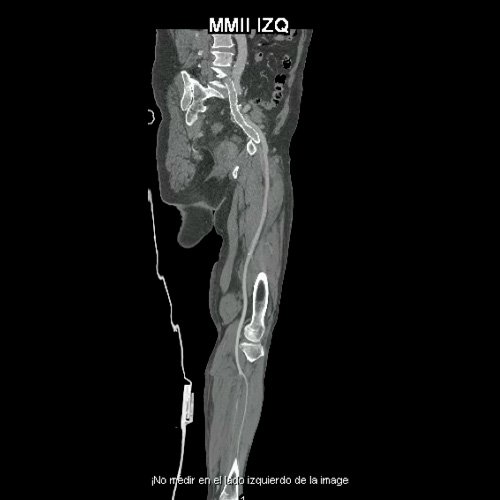

• AngioTAC de miembros inferiores (Día 0): Ateromatosis parietal calcificada parcheada en todo el territorio aorto-ilíaco-femoral bilateral. LADO DERECHO: Arteria ilíaca interna: de calibre y trayecto conservado, permeable. Arterias ilíaca externa y femoral común: de calibre y trayecto conservados, permeables. Arterias circunfleja ilíaca superficial y epigástrica superficial: de calibre y trayecto conservados, permeables. Arteria femoral superficial: de calibre y trayecto conservado, permeable. Arteria femoral profunda: de calibre y trayecto conservado, permeable. Arterias circunflejas femoral medial y lateral: de calibre y trayecto conservados, permeables. Arteria poplítea: de calibre y trayecto conservado, permeable. Arteria tibial anterior: de calibre y trayecto conservado, permeable. Arteria tibial posterior: de calibre y trayecto conservado, permeable. Cambios artrodegenerativos coxo-femorales y tricompartimentales en la rodilla. Signos de entesopatía cuadricipital distal. No se observan alteraciones a nivel de los grupos musculares visualizados. La disposición del tejido graso es normal. LADO IZQUIERDO: En fase angiográfica se observa menor calibre y opacificación de las arterias femoral superficial y profunda, poplítea y de sus ramas musculares en muslo y pierna en comparación con el miembro contralateral, con opacificación arterial preservada. En fase venosa se evidencia mayor la densidad endovascular de las mismas hasta el tercio distal de la pierna, donde se logran identificar a las arterias peronea, tibial anterior y tibial posterior. Se evidencia un defecto de relleno de la vena ilíaca común izquierda, en su nacimiento, en relación a trombosis venosa profunda. No se identifica compromiso de la porción visualizada de la vena cava inferior ni del sistema venoso ilíaco contralateral. Se visualiza aumento del tamaño de todos los grupos musculares del muslo izquierdo con respecto al contralateral y retardo de la concentración de contraste, asociado a edema de los tejidos blandos superficiales. Reticulación de la grasa de la región inguinal. Cambios artrodegenerativos coxo-femorales y tricompartimentales en la rodilla. Signos de entesopatía cuadricipital distal. No se observan alteraciones a nivel del fémur ni de las porciones visualizadas de la tibia y el peroné.

• AngioTAC de miembros inferiores (Día 2): Ateromatosis parietal calcificada parcheada en todo el territorio aorto-ilíaco-femoral bilateral. LADO DERECHO: Arteria ilíaca interna: de calibre y trayecto conservado, permeable. Arterias ilíaca externa y femoral común: de calibre y trayecto conservados, permeables. Arterias circunfleja ilíaca superficial y epigástrica superficial: de calibre y trayecto conservados, permeables. Arteria femoral superficial: de calibre y trayecto conservado, permeable. Arteria femoral profunda: de calibre y trayecto conservado, permeable. Arterias circunflejas femoral medial y lateral: de calibre y trayecto conservados, permeables. Arteria poplítea: de calibre y trayecto conservado, permeable. Arteria tibial anterior: de calibre y trayecto conservado, permeable. Arteria tibial posterior: de calibre y trayecto conservado, permeable. Vena ilíaca primitiva: 13 mm, vena ilíaca externa 11 mm, vena ilíaca interna 7 mm. LADO IZQUIERDO: En esta ocasión, en fase angiográfica se observa de calibre y opacificación conservada de las arterias femoral superficial y profunda, poplítea y de sus ramas musculares en muslo y pierna. En fase venosa se evidencia un defecto de relleno endoluminal de la vena primitiva izquierda que impresiona extenderse actualmente a la vena iliaca externa, a la vena femoral superficial y poplítea, hasta nivel del hueco homonimo, las cuales se visualizan aumentadas de calibre con respecto a sus contralaterales, en relación a trombosis venosa profunda. Se sugiere cotejar con ecodoppler de miembros inferiores. No se identifica compromiso de la porción visualizada de la vena cava inferior ni del sistema venoso ilíaco contralateral. Se visualiza dispositivo vascular en VCI (filtro VCI), infrayacente a las venas renales. Presenta aumento del diámetro del muslo izquierdo con respecto a su contralateral, asociado a edema de los tejidos blandos superficiales. Reticulación de la grasa de la región inguinal a predominio izquierdo con algunas burbujas aéreas. Se observa inmediatamente infrayacente a los antes mencionado, un área hiperdensa que realza en fase venosa, con centro hipodenso, que mide 2.2 cm x 1.4 cm, ya visualizado en tomografía previa. Cambios artrodegenerativos coxo-femorales y tricompartimentales en la rodilla. Signos de entesopatía cuadricipital distal. No se observan alteraciones a nivel del fémur ni de las porciones visualizadas de la tibia y el peroné. Arteria ilíaca interna: de calibre y trayecto conservado, permeable. Arterias ilíaca externa y femoral común: de calibre y trayecto conservados, permeables. Arterias circunfleja ilíaca superficial y epigástrica superficial: de calibre y trayecto conservados, permeables. Arteria femoral superficial: de calibre y trayecto conservado, permeable. Arteria femoral profunda: de calibre y trayecto conservado, permeable. Arterias circunflejas femoral medial y lateral: de calibre y trayecto conservados, permeables. Arteria poplítea, tibial anterior y tibial posterior: de calibre disminuido con respecto a su contralateral, permeables. Vena ilíaca primitiva: 14 mm, vena ilíaca externa 17 mm, vena ilíaca interna 9 mm. Calcificaciones en conducto inguinal bilateral. Hidrocele bilateral.

Angio TAC de miembros inferiores (Día 0)

Angio TAC de miembros inferiores (Día 2)

Flebotomografia de miembros inferiores (Día 18)